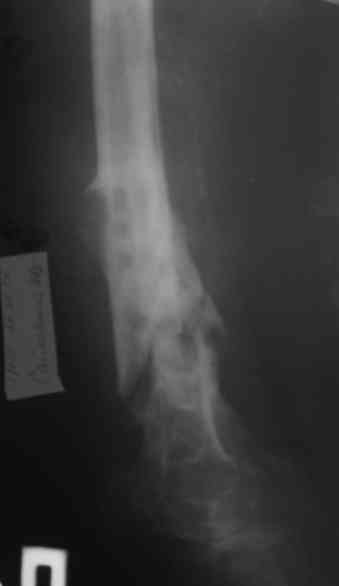

Уважаемые коллеги! Пациент лечился по поводу перелома н/3 бедра 1 год назад.

В настоящий момент: Несросшийся перелом н/3 правого бедра. Остеомиелит, свишевая форма.Контрактура коленного сустава.

Привет. Я имел в виду предложенную Вами программу лечения. Поражение кости остеомиелитическим процессом (судя по рентгенограммам) не канальное - когда спейсер можно поставить в канал после санации на какое-то время, а по всей окружности кости - когда придется делать спейсер в виде простой "болванки на арматуре). Вероятнее всего при хорошей санации получится дефект и укорочение. При втором этапе (как я понял, вы планируете БИОС) не факт, что восстановите длину и не "полыхнет" инфекция. Поэтому и предложена другая программа. Ваше право выбора - удачи на сложном пути избавления больного от ятрогенного о\миелита. Если проинформируете, что получилось, спасибо.